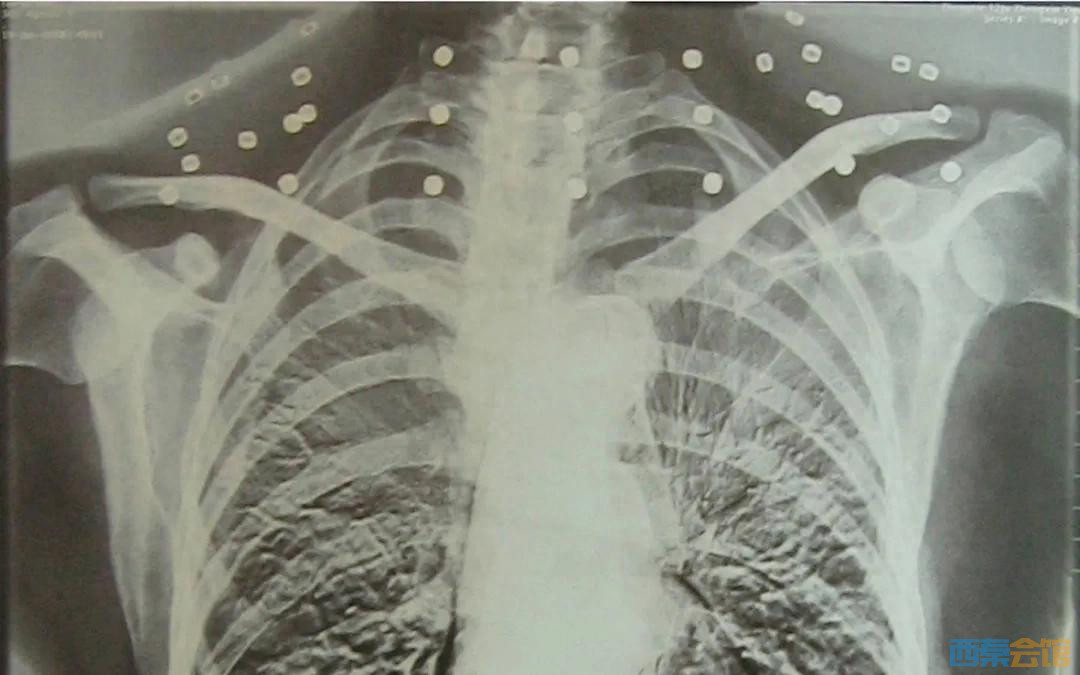

“老先生 您要把项链取下来再做CT” “我从来没戴过项链 你看会不会是弹片?” 这张照片 是今年82岁的吴以先老人 拍摄的一张CT照 20年前 吴以先在一次做CT检查时 医生误以为他戴了项链 于是提醒要取下来再做检查 但实际上是 吴以先的颈部和腹部 共分布着33枚弹片 无意间的对话 揭开了吴以先老人 一段不平凡的往事 1965年 吴以先是一名铁道兵 作为中国后勤部队 一支队三大队十六连的重机枪手 参与了援越抗美战役 一天,防空警报突然响起 美军即将进行轰炸 担任重机枪弹药手的吴以先 和战友密切配合 对前来的美军敌机进行反击 吴以先回忆 当时美军敌机飞得不高 同时发射了两种炮弹 一种是火箭炮,一种是“菠萝弹” “一个‘菠萝弹’炸出了脸盆大的坑 里面装着钢珠,钢珠杀伤力很强 弹片炸到我身上来了” 虽然身负重伤 但吴以先继续配合机枪手对空扫射 直到亲眼看着美军敌机逃离 他才被战友送医抢救 当时,**把他的小腹打穿了  经过7小时手术 吴以先奇迹般挺了过来 但是打进身体里的弹片 一直留在了体内 被打穿的右手康复后也是扭曲的 吴以先说 “我来是为了保家卫国 为了世界和平 我要是牺牲了,也是光荣的”  养好伤后,吴以先准备归队 却收到了一张残疾军人证 组织准备让他复员回家 并给他安排好了工作 但吴以先想也不想就拒绝了 他说 “残疾军人证我坚决不要 我那么年轻,我还能劳动 不要国家把我养起来 我还能出一份力” 经过多次争取 最终,组织批准吴以先重返连队 主要从事后勤工作  为了不让家人担心 养伤期间 吴以先对家人隐瞒了伤情 但是右手受伤 写字成了大问题 他只好用左手给家人写信 吴以先的妻子谭运莲回忆: “每当看到信,我就很高兴 结果一拆开 东一笔、西一笔 他骗我说是右手长疮 写不好,才用左手写的”  后来虽然伤势好转 但是吴以先的右手落下了残疾 直到现在 他体内的弹片都没有取出 每到天气变化时 身体留有弹片的位置就有痛感 但吴以先不考虑取出弹片 在他看来 这是他与战友并肩作战的见证 是他的勋章  吴以先一直在 组织安排的岗位上工作到退休 从没有因“英雄”身份 而寻求特殊待遇 他说 比起那些英勇牺牲的战友们 能活下来已经很幸运了 组织需要他做什么,他就做什么  退休后 他还接下了社区楼长 和党支部书记的工作 不求待遇 只求更好地为大家服务 他说,活到老、学到老、奉献到老  岁月虽逝,硝烟散去 但那份军人的荣耀与担当 与吴以先身上那33枚弹片 一起永远烙印在他心中 33枚“军功章” 是一名军人的光荣 也是一位英雄的至诚本色 致敬! (来源:央视新闻)